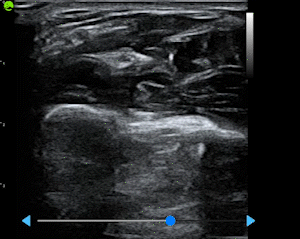

Built from a dataset of millions de-identified ultrasound images, our AI models cover Obstetrics, Cardiology, and Gynecology. They analyze key anatomical structures in real time, providing accurate biometric measurements and insights that help clinicians assess fetal growth, cardiac function, and organ health with greater speed and confidence.

AI Powered Acquisition

- Real-time guidance during scanning

- Automatic quality assessment

- Reduced operator variability

- Faster scan completion